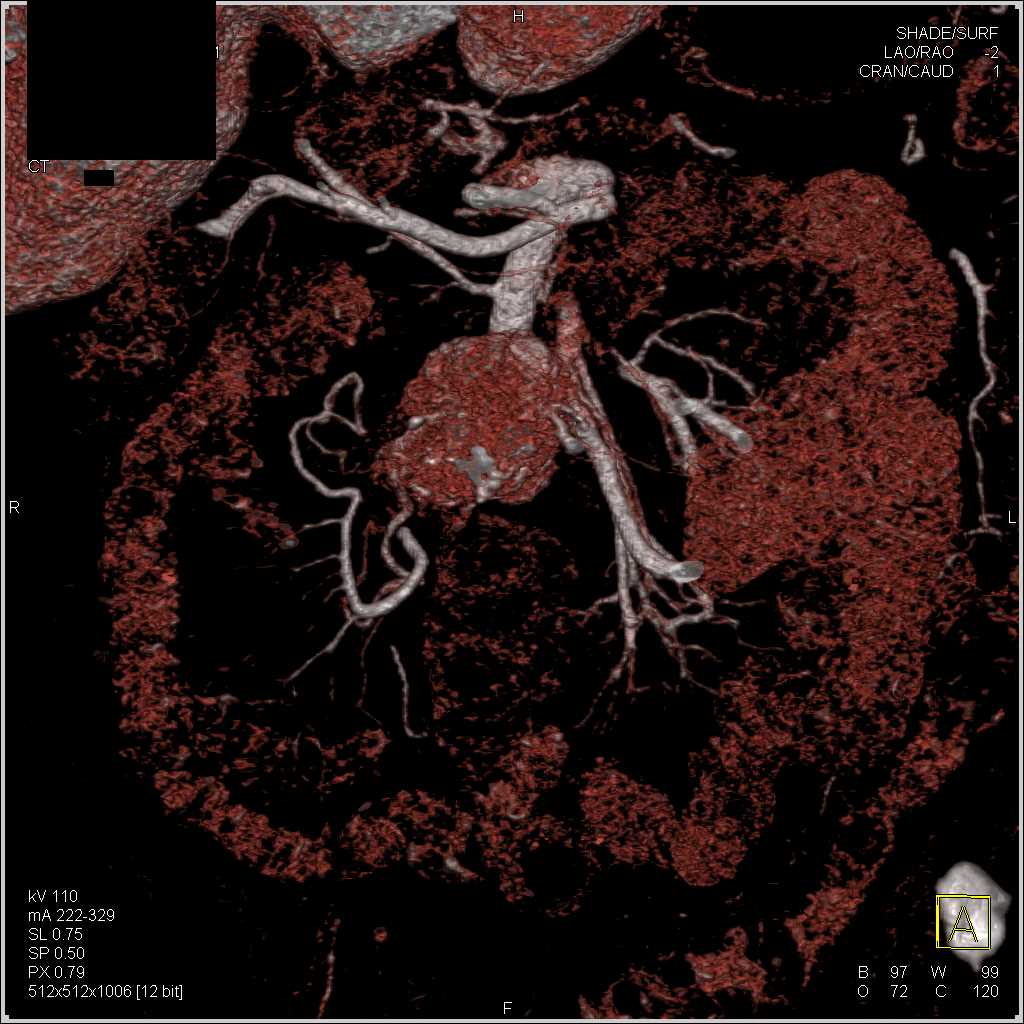

Carcinoid Tumor with Desmoplastic Reaction